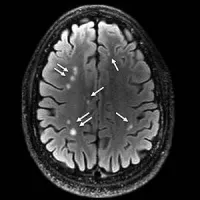

Figure 1. Coronal images derived from tract-based spatial statistics results and rendered on T1-weighted MR images from the Montreal Neurological Institute atlas show how patients with depression have significantly decreased fractional anisotropy in the region of A, the right nucleus accumbens (arrow) or “reward centre,” as well as B, the anterior limb of the internal capsule (arrow) and C, the superior longitudinal fasciculus (arrow) — regions that are involved in depressive disorders in non-traumatic and traumatic settings.